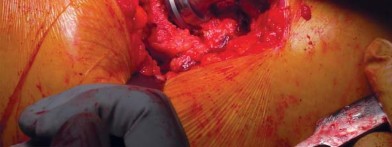

تحضير الفخذ والحق

يتم تحديد مستوى قطع عنق الفخذ مسبقًا بالتخطيط (باستخدام الأشعة السينية) ومواءمته أثناء الجراحة مع المدور الكبير. بعد قطع عنق الفخذ، يتم تحضير الحُق بالطريقة القياسية قبل تحضير الفخذ. يفضل الأستاذ الدكتور محمد هطيف عادةً وضع الكأس وفقًا للمعالم التشريحية لإعادة إنشاء التوجيه الطبيعي للحُق لدى المريض ويتحقق من الإصدار والميل الصحيحين عن طريق الجس والرؤية المباش